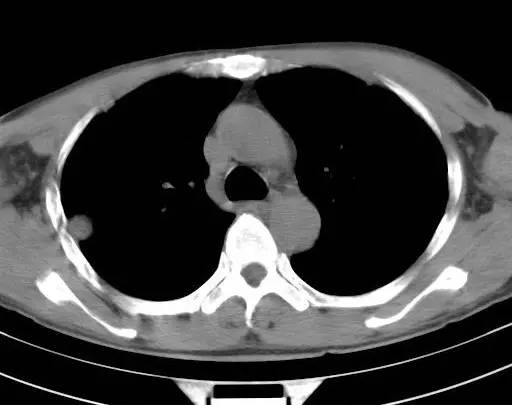

治疗前CT(图1-8):两肺胸膜下散在多发斑片状、结节状伴空洞影,边缘欠清晰。